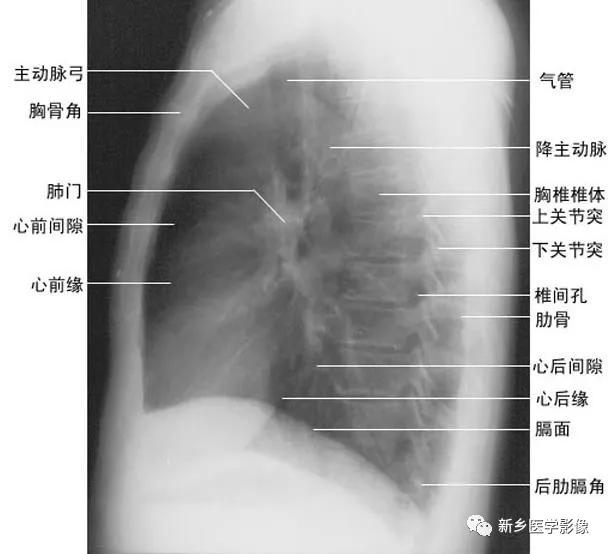

(二)叶间胸膜转折(叶间裂) 1、斜裂 一般在正位片上不能显示.在侧位片上表现为自后上斜向前下的线条状阴影:右德斜裂的后端起始于第4、5胸椎水平,斜向前下方走行,止于膈面距前缘2~3cm处,与膈顶部的水平面约成50°角;左侧斜裂后端起始点较右侧稍高,在第3~4后肋端水平,因而其倾斜度也较右饲稍大,前下端达肺的前下角处,与膈顶水平面约成60°角。叶间胸膜面通常略有弯曲,斜裂上半部稍斜向外,下半部稍斜向内,故在侧位片上可成s形。

2、横裂又称水平裂,约70%的人正、撼位胸片均可显影。在正位片上表现为右中肺野横行细线状阴影,从第6肋腋部水平自外向内延伸.并止于肺门外lcm处。可向上或向下倾斜10:左右或略成曲线;在侧位片上,横裂起白斜裂中部,向前呈水平方向走行达前胸壁。其位置的改变可作为判断肺体积变化的标志(如上图)。 某些正常人可发生叶间裂不分、分裂不全或出现多余叶间裂等变异情况,因而叶间胸膜也发生相应的变化(参阅肺副叶)。

2、侧位肺门 侧位胸片上,两饲肺门阴影大部分重叠,若以侧位气管轴线为界,右肺门略信其前下,左肺门大部分在其后上。侧位肺门影前缘为右上肺静脉干形成的椭圆形阴影,前后径为2cm左右;中间纵行透亮区为气管及气管分叉,其内圆形透亮影表示支气管开口,右侧在上,左侧居下;后上缘为左肺动脉弓,下缘由两下肺动脉构成下行的树枝状影。因此,侧位肺门影似一尾巴拖长的“逗号”(如上右图):

在正位胸片上,膈显示为圆顶状阴影,边缘光滑整齐,顶峰靠近中内1/3处。内侧与心脏形成心膈角。外侧与胸壁相交形成肋膈角;在侧位片上,圆顶部靠前,前端与前胸壁形成前肋膈角,后部与后胸壁形成后肋膈角,正常时前、后肋膈角均为锐角,后肋膈角位置最低。右膈顶的位置,一般与第6前肋或第10后肋等高,多数人右膈比左膈高1~2cm,这是因为心脏位置偏于胸腔左侧,故而将左膈压低。膈的位置在正常时可有若干变动:例如儿童膈位置较高,老年人则较低;矮胖型膈位置较高,瘦长型则较低;卧位时膈位置较高,立位时则较低;呼气时膈位置较高,吸气时则较低等。

标准右前斜位(又称第一斜位)为后前位向左旋转约45。所得影像。心前缘自上而下由主动脉弓曼升主动脉、肺动脉、右心室漏斗部、右心室前壁和左心室下端构成。升主动脉前缘平直,弓部则在上方弯向后行;肺动脉段和漏斗部稍为隆起;心尖以上大部分为右心室构成。心前缘与胸壁之间有尖向下的三角形透明区称为心前间隙。心后缘上段为左心房,下段为右心房,两者无清楚分界。心后缘与脊柱之间透明区称心后间隙,食管在心后间隙通过,钡剂充盈时显影。右前斜位主要观察右室流出道及左心房大小(如下图)。

(四)左侧位 心影从后上向前下倾斜,心前缘下段为右心室前壁,上段则由右心室漏斗部与肺动脉主干构成,再苣上为升主动脉前壁,直向上走行。这些结构与翦髓壁之间的三角形透亮区称为胸骨后区。心后缘上中段由左心房构成,下段则由左心室构成。心后下缘、食管与膈之间的三角形间隙,为心后食管前间隙(如下图)。